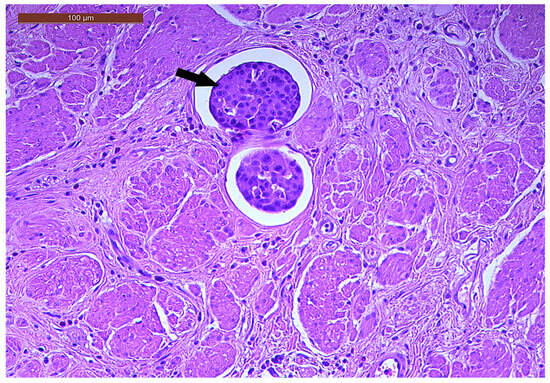

LVI was detected in 31 cases (51.7%), and perineural invasion (PnI) was identified in 20 cases (33.3%) (Figure 1 and Figure 2). EMVI and IMVI were registered in 31 (51.7%) and 21 cases (35%), respectively. Regarding Bd and PDC categories, a significant proportion of tumors were recorded as Bd1, while Bd2 was less common (49 cases; 81.6% vs. 7 cases; 11.7%) (Figure 3); moreover, a large proportion were classed as the PDC1 grade (Figure 4), while the PDC2 grade was less common (55 cases; 91.7% vs. 4 cases; 6.7%). The main clinicopathological characteristics of the study group are summarized in Table 4.

Figure 3. Individual and small clusters of tumor cells (arrows) at the invasive tumor front in a ypT3-stage LARC case (Bd2) (H&E staining, 200×).